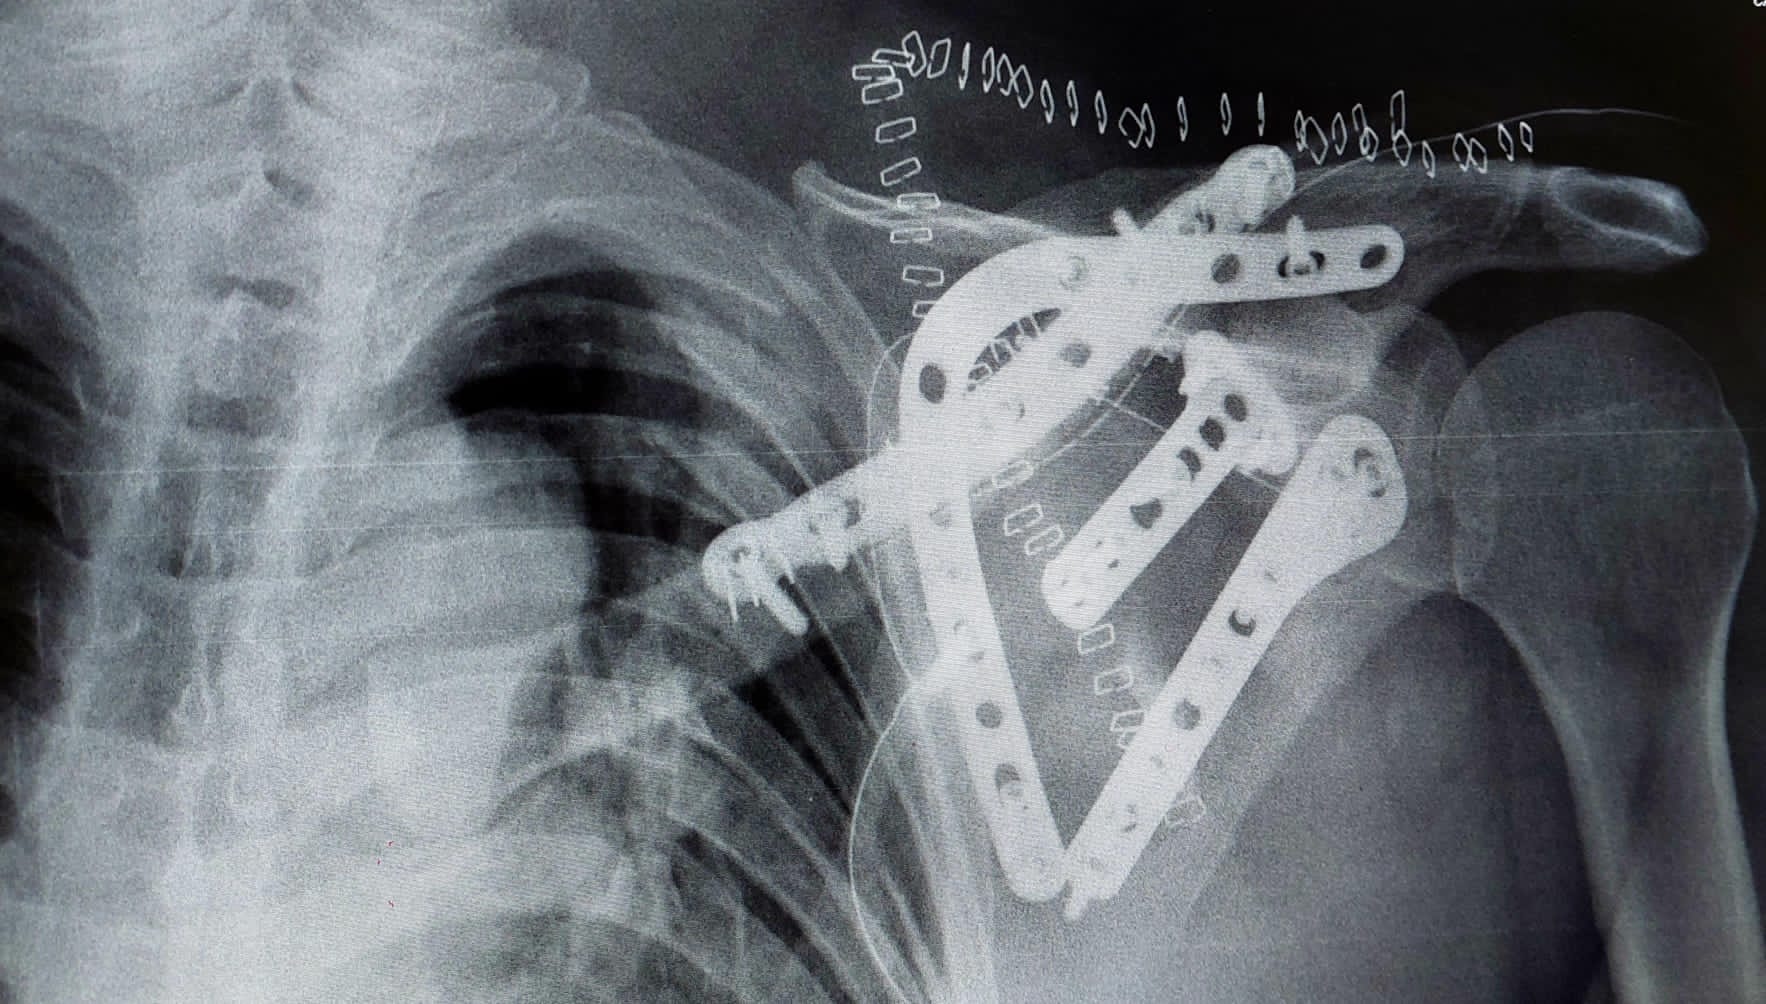

¿Y las placas metálicas, prótesis y tornillos?

Aquí hay mucha confusión y depende de la composición de la prótesis. La evidencia y los fabricantes hacen un matiz importante:

- La magnetoterapia está contraindicada en prótesis magnetizables (metales antiguos o ferromagnéticos).

- En prótesis modernas (titanio u otros materiales no ferromagnéticos), en general no hay problema, y de hecho se usa a menudo en pacientes operados con fijación interna (Globus tiene programas específicos para utilizar sobre prótesis de rodilla o de cadera)

Si tienes prótesis o placas metálicas y no sabes de qué material son, consulta primero con tu traumatólogo. Si ya te han hecho una resonancia magnética sin problemas, es muy probable que la prótesis sea compatible con magnetoterapia.